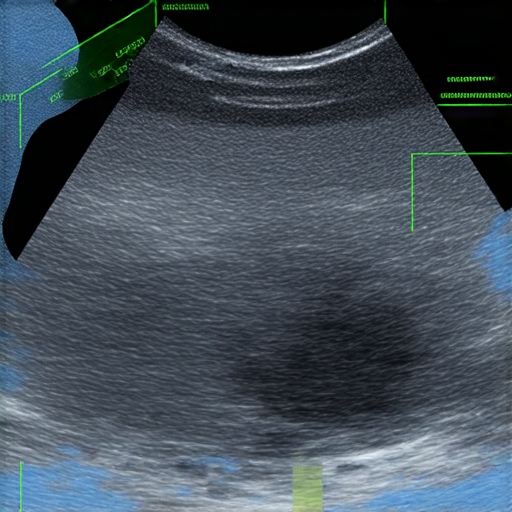

盆腔超聲波檢查過程中的醫療設備與檢查結果圖示,展示健康秘密與診斷資訊,讓你了解盆腔健康與疾病預防,提升英語能力,促進健康意識。

盆腔超聲波檢查是一種非侵入性的影像檢查技術,主要用於檢查女性的生殖器官,包括子宮、卵巢及其他相關結構。透過使用聲波,醫生可以清楚看到這些器官的形狀和大小,幫助診斷各種潛在的健康問題。